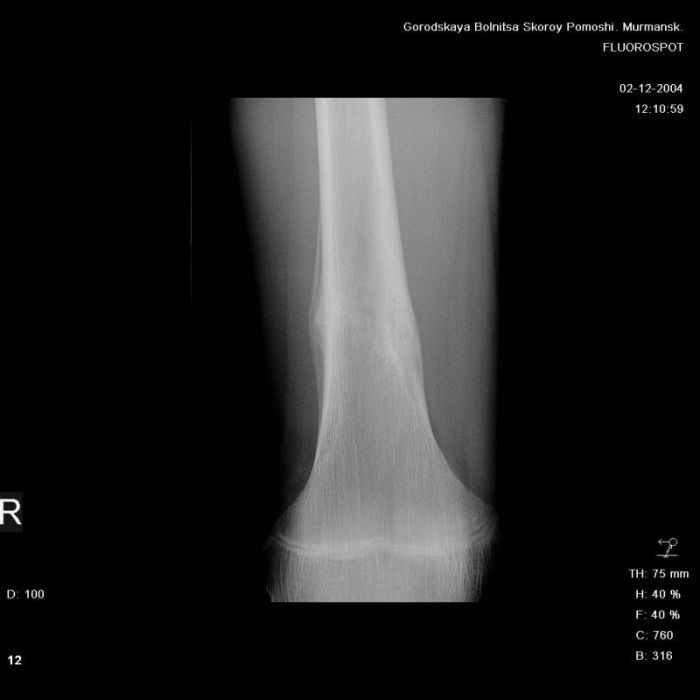

Здравствуйте, уважаемые коллеги!Представляю вашему вниманию интересный случай и пока что непонятный для меня в диагностическом плане. На днях в наше отделение (детской ортопедии и травматологии) поступил 13-летний мальчик по направлению из поликлиники с диагнозом: остеома нижней трети правого бедра.

Анамнез практически никакой: в следствие травмы (растяжение связок коленного сустава) от 07.11.2004 выполнены Rg-граммы в травмпункте и обнаружено опухолевидное образование. Первичные Rg-граммы я не публикую, так как они заметно худшего качества, да и динамики за прошедшие три недели не отражают. Болевой синдром купирован в течение трёх дней. В настоящий момент мальчика ничего не беспокоит. Ходьба не нарушена, опухоль пальпируется с трудом по задней поверхности в н\3 правого бедра, пальпация безболезненна, объем движений в суставах правой нижней конечности полный и симметричный. Кожа над опухолью не изменена.В нашей клинике проведено дополнительное обследование: общие анализы крови и мочи, биохимия крови без особенностей. Выполнены Rg-граммы на цифровом Siemens обычные и продольные томограммы срезами 3-5 мм, а также компьютерная томография поперечными срезами по 5 мм. Прошу обратить внимание, что на приведённых томограммах видны две полости 10х15 мм и 15х60 мм. Также имеются два опухолевидных образований наслаивающихся друг на друга: уплощённое и вытянутое 10х100 мм и элипсовидной формы 15х30 мм. Это хорошо заметно на фото a_1.jpg c_1.jpg и d_1.jpg. Плотность внутри полостей 125% от плотности костномозгового канала, плотность наружного опухолевидного образования 55% от плотности кортикального слоя. Также отмечается линия перелома по центру наружного опухолевидного образования.Исходя из полученных данных мнения в плане диагноза несколько разделились от 1)сочетания кортикальной фиброзной дисплазии и латентно протекавшего маршевого перелома н\3 правого бедра до 2)остеосаркомы. В отношении первого варианта не сходится отсутствие клиники при переломе такой крупной кости как бедро, второй вариант вообще оставлю без комментария, ибо некомпетентен. Хотелось бы услышать мнения коллег, с удовольствием ознакомлюсь с любыми предположениями и замечаниями.С уважением, Александр Е. КлоковОтделение детской ортопедии и травматологииБСМП г. Мурманска.